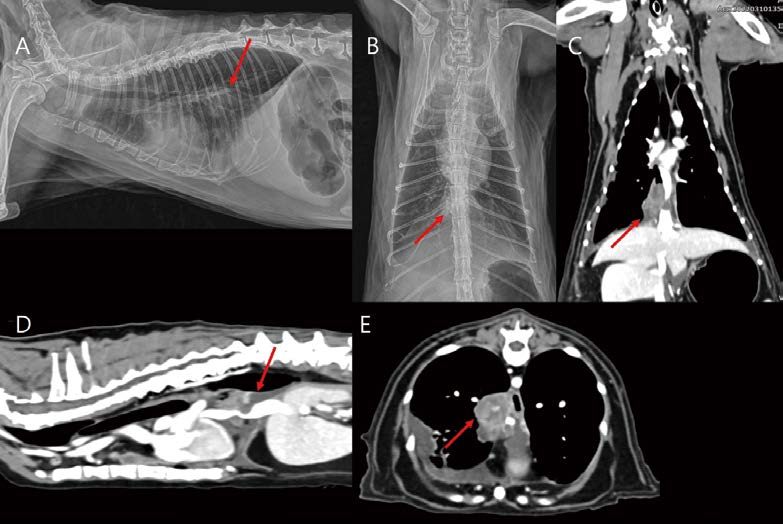

[대한수의사회지 24.png

폐엽 절제술 이후 환자의 상태가 양호하여 보호자님은 항암 치료를 일단 보류하셨는데, 수술 1년 후 흉부 방사선 검사에서 좌측 후엽의 작은 결절성 음영이 관찰되었습니다(A, B). CT 검사에서 이전 우측 전엽 lymphoma와 유사한 소견이 좌측 후엽에서 관찰되었습니다(C, D, E). CHOP 항암 치료를 시작하였고, 4개월 뒤 CT 검사에서 폐 병변은 모두 개선되었습니다. CHOP 항암 치료 종료 후 잘 지내다가, 초진(우측 전엽 병변 발견) 2년 10개월 뒤 식욕부진 빈혈로 내원하였습니다. 복부초음파 검사에서 hepatomegaly, splenomegaly with honeycomb pattern이 관찰되었습니다. 간, 비장 FNA에서 Multicentric lymphoma 상태로 확인되었습니다. 다시 CHOP 항암치료 시작하였으나, 2개월 뒤 사망하였습니다.

<여기서 잠깐 비교 증례!>

증례 1과 비교해서 다음 환자는 간헐적으로 숨을 몰아서 쉬는 증상 이외에 식욕, 활력 모두 양호한 고양이입니다. 초진(2년 전) 시 흉부 방사선 검사와 2년 후 촬영된 CT 검사가 거의 유사한 침윤 범위와 밀도를 보입니다. CT에서 multifocal bronchiectasis with mucoid impaction and tiny calcification 양상으로 관찰됩니다(A, B, C, D, E, F). 임상적 경과와 세포학적 검사에서 양성의 폐 질환이 우선 고려되어 모니터링하기로 하였습니다. 이 후 3년째에도 큰 변화(악화/개선) 없이 유사한 흉부 방사선 상태를 보였으나, 결국 pulmonary adenocarcinoma였습니다.

누가 봐도 둥글고 큰 종괴 양상은 폐 종양으로 진단하기가 쉬우나, 실제 임상에서 염증성 변화와 종양성 변화를 감별하기 어려운 경우가 많으며, 시기적으로 다른 염증, 감염, 종양성 변화가 모두 동반된 환자도 많은 것 같습니다. 폐 종양성 변화에 의해 airway obstruction이 발생하면 이차적인 pneumocyte degeneration 때문에 endogenous lipid pneumonia의 원인이 될 수 있다고 알려져 있습니다. 실제 고양이에서 endogenous lipid pneumonia가 bronchogenic carcinoma 또는 intra-lesional infection과 관련된 증례 보고들이 있습니다. 환자의 상태가 양호한 편이고, 영상학적으로 큰 변화 소견이 없을 때, 환자를 긴 시간 동안 모니터링하기 어려운 경우도 많기 때문에 결과를 잘 모르는 상태에서, 환자의 상태는 지속적으로 변화하고 복합적일 수 있는데, 그 동안 수많은 환자를 feline chronic asthmatic bronchitis 또는 lipid pneumonia 등 만성 양성의 하부 호흡기 질환이라고 단순 진단하지 않았나 반성하게 됩니다.